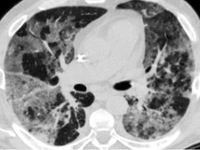

Компьютерная томография: двусторонние области альвеолярного помутнения

Острая интерстициальная пневмония начинается как банальная ОРВИ — с резкого подъема температуры и озноба. Внезапно появляется сильная одышка и приступообразный кашель. Болезнь развивается стремительно и быстро прогрессирует. У пациентов нарастают признаки респираторной недостаточности, отекают стенки альвеол, в них скапливается экссудат, возникает фиброзный процесс. Больным требуется ИВЛ до улучшения общего состояния. В противном случае человек погибает. Это самый опасный вид патологии с высоким процентом летальности.